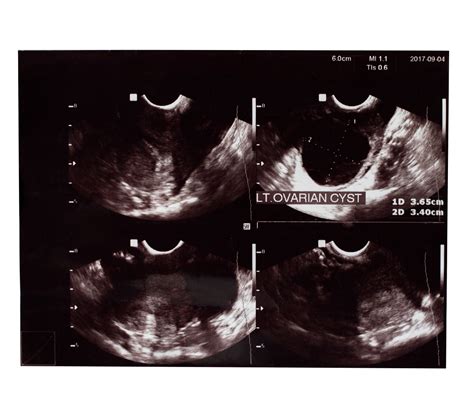

Ciste na jajčnikih: Nekatere vrste cist, kot so endometriomi (ciste, povezane z endometriozo) ali ciste pri sindromu policističnih jajčnikov (PCOS), lahko motijo normalno ovulacijo in s tem plodnost. Laparoskopija omogoča natančno odstranitev teh cist, kar pogosto vodi do izboljšanih reproduktivnih rezultatov. Pri sindromu policističnih jajčnikov se lahko s posebnim laparoskopskim posegom, imenovanim "navrtanje" ali laparoskopska elektrokavterizacija (LEKO) jajčnikov, ustvari majhne luknjice v jajčniku, ki lahko sprožijo hormonske spremembe in povzročijo ovulacijo.